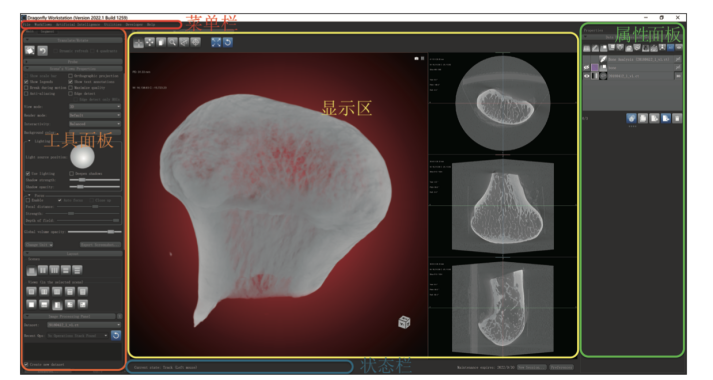

考虑到 Python语言易上手的特点及其在人工智能领域的广泛应用,读者选用了三维图像专业处理软件 Dragonfly作为本书的软件工具,它是一款广泛应用于科研领域的图像处理软件,为用户提供了一个易使用且功能强大的人工智能应用平台,入手门槛较低。

针对多元化受众的不同需求,小异发现书籍给出了非常细致的落地讲解,宛如一本“看书说话”的文字版教程。作者把软件下载、安装、软件界面介绍这些内容都囊括进来,就是为了照顾医学背景读者对编程不熟悉的特殊情况。

图:书中介绍界面和展示编程效果的内容